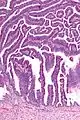

The name of the lesion describes it microscopic appearance. It has nipple-like structures with fibrovascular cores (papillae) that are long in relation to their width (villus-like), which are covered with a glandular pseudostratified columnar epithelium.

Intermediate magnification